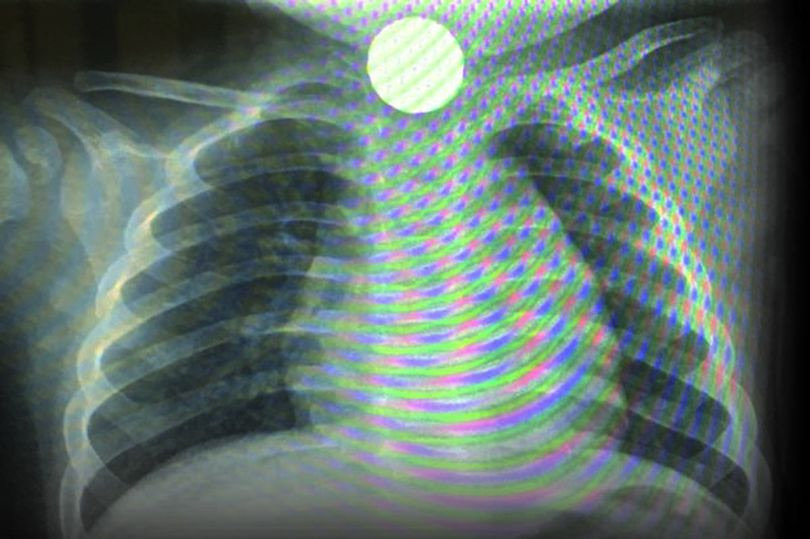

스카일라의 상태를 본 헐 로얄 병원 의사들은 알러지 반응 때문에 기도가 좁아졌을 가능성을 제일 먼저 내놓았습니다. 그러나 X레이 사진을 찍어 보니 선명한 원형 물체가 아기의 가슴 속에 자리잡고 있는 게 보였습니다.

케일리 씨는 “페니 동전이 걸려있다는 걸 본 순간 눈물이 터져 오열했어요”라고 말했습니다. 의사들도 깜짝 놀라 순간 말을 잃었습니다.